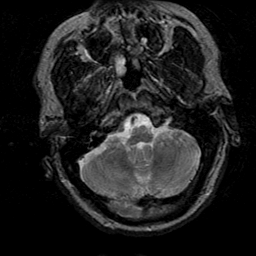

Subacute Stroke, overlay -- Slice #4

[Home][Help][Clinical] Slice 4